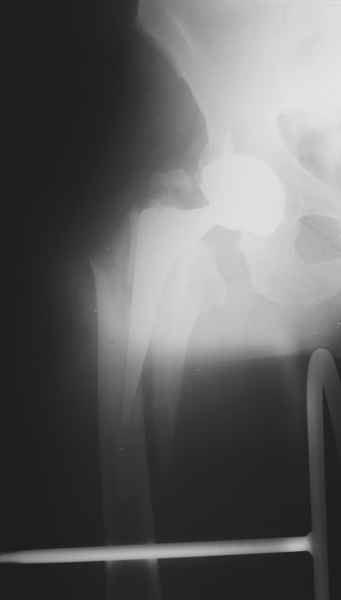

Пациенту 72 года, оперировался 11 лет назад в ГКБ15 Москва. Судя по снимку ножка споторно фирмы матис. Вряд ли сможем найти такую же для примерки.

Дополнительные снимки